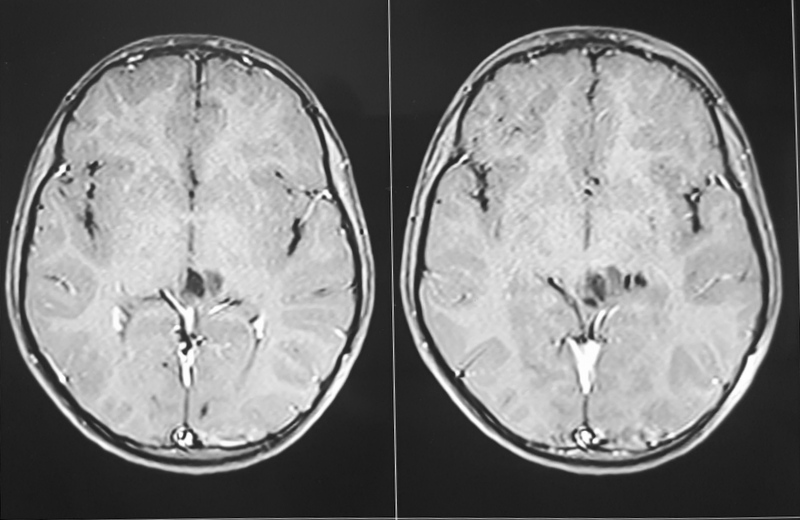

A 38-year-old-male was admitted with sudden onset of severe global headache and vomiting, followed by altereation in sensorium. CT brain showed subarachnoid and intraventricular hemorrhage (Fig 1). MRI brain revealed deep seated right sided thalamic hematoma due to ruptured internal carotid artery bifurcation aneurysm (Fig 2), confirmed by cerebral digital subtraction angiography (Fig 3). He underwent clipping of the aneurysm by transciliary supraorbital keyhole minicraniotomy (see video). Postoperative angiography showed complete occlusion of the aneurysm (Fig 4). When discharged ten days later, there was no neurological deficit (Fig 5).

Fig 2

(Fig 2)